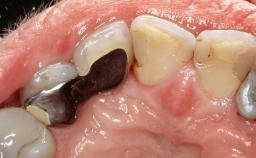

In this case, Myroslav Solonko, Ignacio Sanz Sánchez and Mariano Sanz present a treatment that aims to eliminate exposed implant threads by modifying the implant surface, converting a moderately-rough surface into a smooth surface.

A 63-year-old male patient was referred to the post-graduate periodontal clinic of the Complutense University of Madrid for the treatment of peri-implantitis. According to the patient’s record, all his maxillary teeth had been extracted ten years previously due to severe periodontitis, and a full-mouth implant-supported restoration on eight implants was placed. No supportive periodontal therapy was provided apart from occasional check-ups by the restorative dentist.